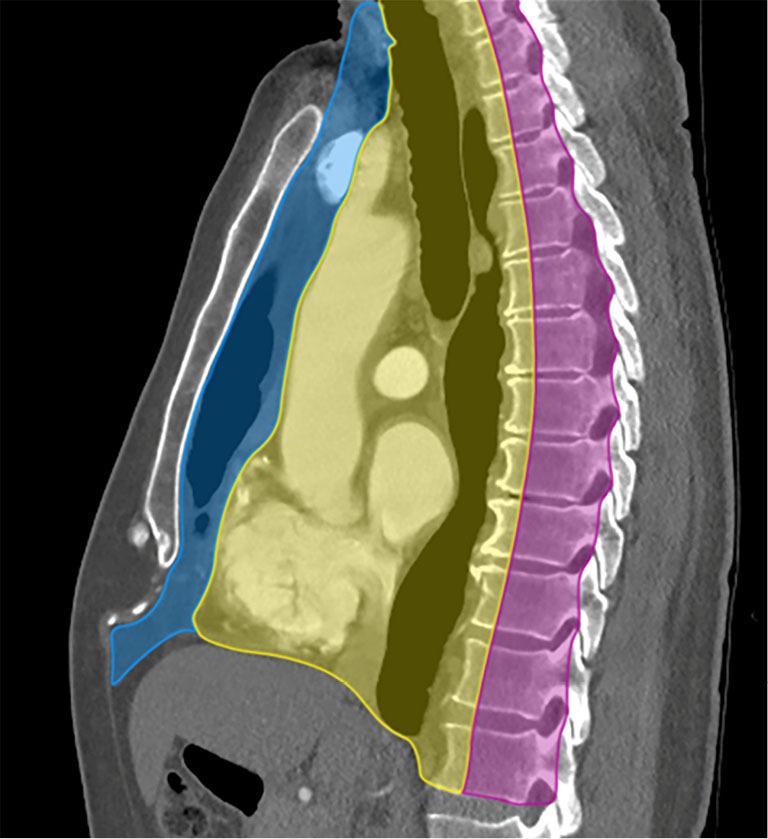

纵隔肿块及类似病变的多模态成像

Multimodality imaging of mediastinal masses and mimics.

A wide variety of neoplastic and nonneoplastic conditions occur in the mediastinum. Imaging plays a central role in the evaluation of mediastinal pathologies and their mimics. Localization of a mediastinal lesion to a compartment and characterization of morphology, density/signal intensity, enhancement, and mass effect on neighboring structures can help narrow the differentials. The International Thymic Malignancy Interest Group (ITMIG) established a cross-sectional imaging-derived and anatomy-based classification system for mediastinal compartments, comprising the prevascular (anterior), visceral (middle), and paravertebral (posterior) compartments. Cross-sectional imaging is integral in the evaluation of mediastinal lesions. Computed tomography (CT) and magnetic resonance imaging (MRI) are useful to characterize mediastinal lesions detected on radiography. Advantages of CT include its widespread availability, fast acquisition time, relatively low cost, and ability to detect calcium. Advantages of MRI include the lack of radiation exposure, superior soft tissue contrast resolution to detect invasion of the mass across tissue planes, including the chest wall and diaphragm, involvement of neurovascular structures, and the potential for dynamic sequences during free-breathing or cinematic cardiac gating to assess motion of the mass relative to adjacent structures. MRI is superior to CT in the differentiation of cystic from solid lesions and in the detection of fat to differentiate thymic hyperplasia from thymic malignancy.

纵隔可发生各种各样的肿瘤性和非肿瘤性疾病。影像学在纵隔病变及其类似病变的评估中起着核心作用。将纵隔病变定位到某个分区,并对其形态、密度/信号强度、强化情况以及对邻近结构的占位效应进行特征描述,有助于缩小鉴别诊断范围。国际胸腺恶性肿瘤研究小组(ITMIG)建立了一种基于横断面成像和解剖学的纵隔分区分类系统,包括血管前(前)、内脏(中)和椎旁(后)分区。横断面成像在纵隔病变评估中不可或缺。计算机断层扫描(CT)和磁共振成像(MRI)有助于对X线检查发现的纵隔病变进行特征描述。CT的优点包括广泛可用、采集时间短、成本相对较低以及能够检测钙化。MRI的优点包括无辐射暴露、软组织对比分辨率高,能够检测肿块跨越组织层面的侵犯情况,包括胸壁和膈肌、神经血管结构受累情况,以及在自由呼吸或电影式心脏门控期间进行动态序列成像以评估肿块相对于相邻结构的运动情况。在区分囊性病变与实性病变以及检测脂肪以鉴别胸腺增生与胸腺恶性肿瘤方面,MRI优于CT。